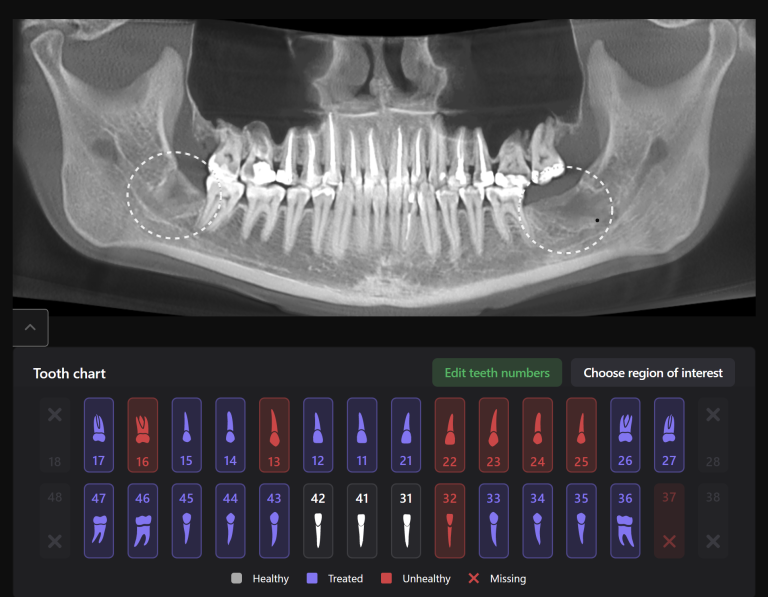

The final result of comprehensive prosthetic rehabilitation with Diagnocat AI